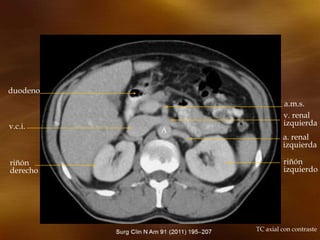

TC axial con contraste

duodeno

v.c.i.

riñón

v. renal

a. renal

a.m.s.